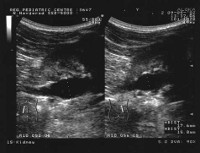

Ранняя диагностика диабетической нефропатии представляет собой важнейшую задачу. С целью установления диагноза диабетической нефропатии проводят биохимический и общий анализ крови, биохимический и общий анализ мочи, пробу Реберга, пробу Зимницкого, УЗДГ сосудов почек.

Важно проводить дифференциальную диагностику диабетической нефропатии с другими заболеваниями почек: хроническим пиелонефритом, туберкулезом, острым и хроническим гломерулонефритом. С этой целью может выполняться бактериологическое исследование мочи на микрофлору, УЗИ почек, экскреторная урография. В некоторых случаях (при рано развившейся и быстро нарастающей протеинурии, внезапном развитии нефротического синдрома, стойкой гематурии) для уточнения диагноза проводится тонкоигольная аспирационная биопсия почки.